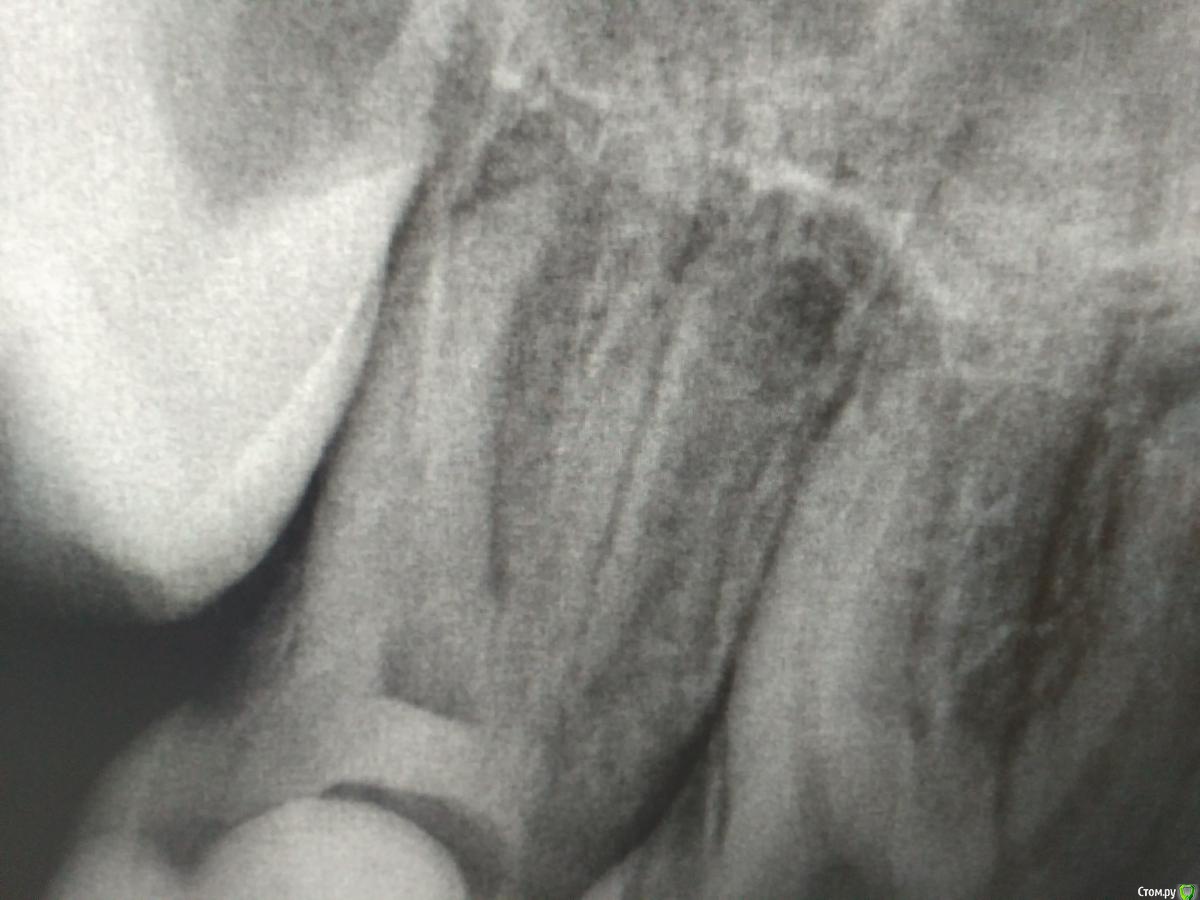

St. Опубликовано 8 января, 2017 Поделиться Опубликовано 8 января, 2017 (изменено) Фрагмент панорамы. Изменено 8 января, 2017 пользователем St. Ссылка на комментарий

Л Ю С Я Опубликовано 8 января, 2017 Поделиться Опубликовано 8 января, 2017 Фрагмент панорамы.Вообще не люблю панорамные снимки при эндо. Апекс дистального совсем не виден. Сделайте хотя бы прицельный. 15 лет, мальчик, возможна открытая верхушка, локатор и не будет работать. Тактика лечения при этом тоже поменяется. Если дело не в этом, продолжаете работать, определив рд по рентгенограмме , само остановиться, обычно у молодых при обострении пульпита всегда кровит сильно пока полностью каналы не очистите. Иногда кальций на 3-4 минуты прямо в кровящий канал помогает Ссылка на комментарий